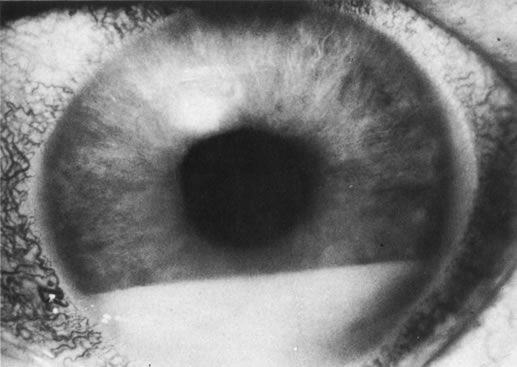

In addition to producing media opacity, inflammation, and cataract, uveal melanomas can also produce other signs that may lead to the incorrect diagnosis of uveitis. Anterior melanomas, especially those that involve the ciliary body, often produce dilated episcleral vessels (sentinel vessels) that occasionally have been misdiagnosed as scleritis (Fig. 6).